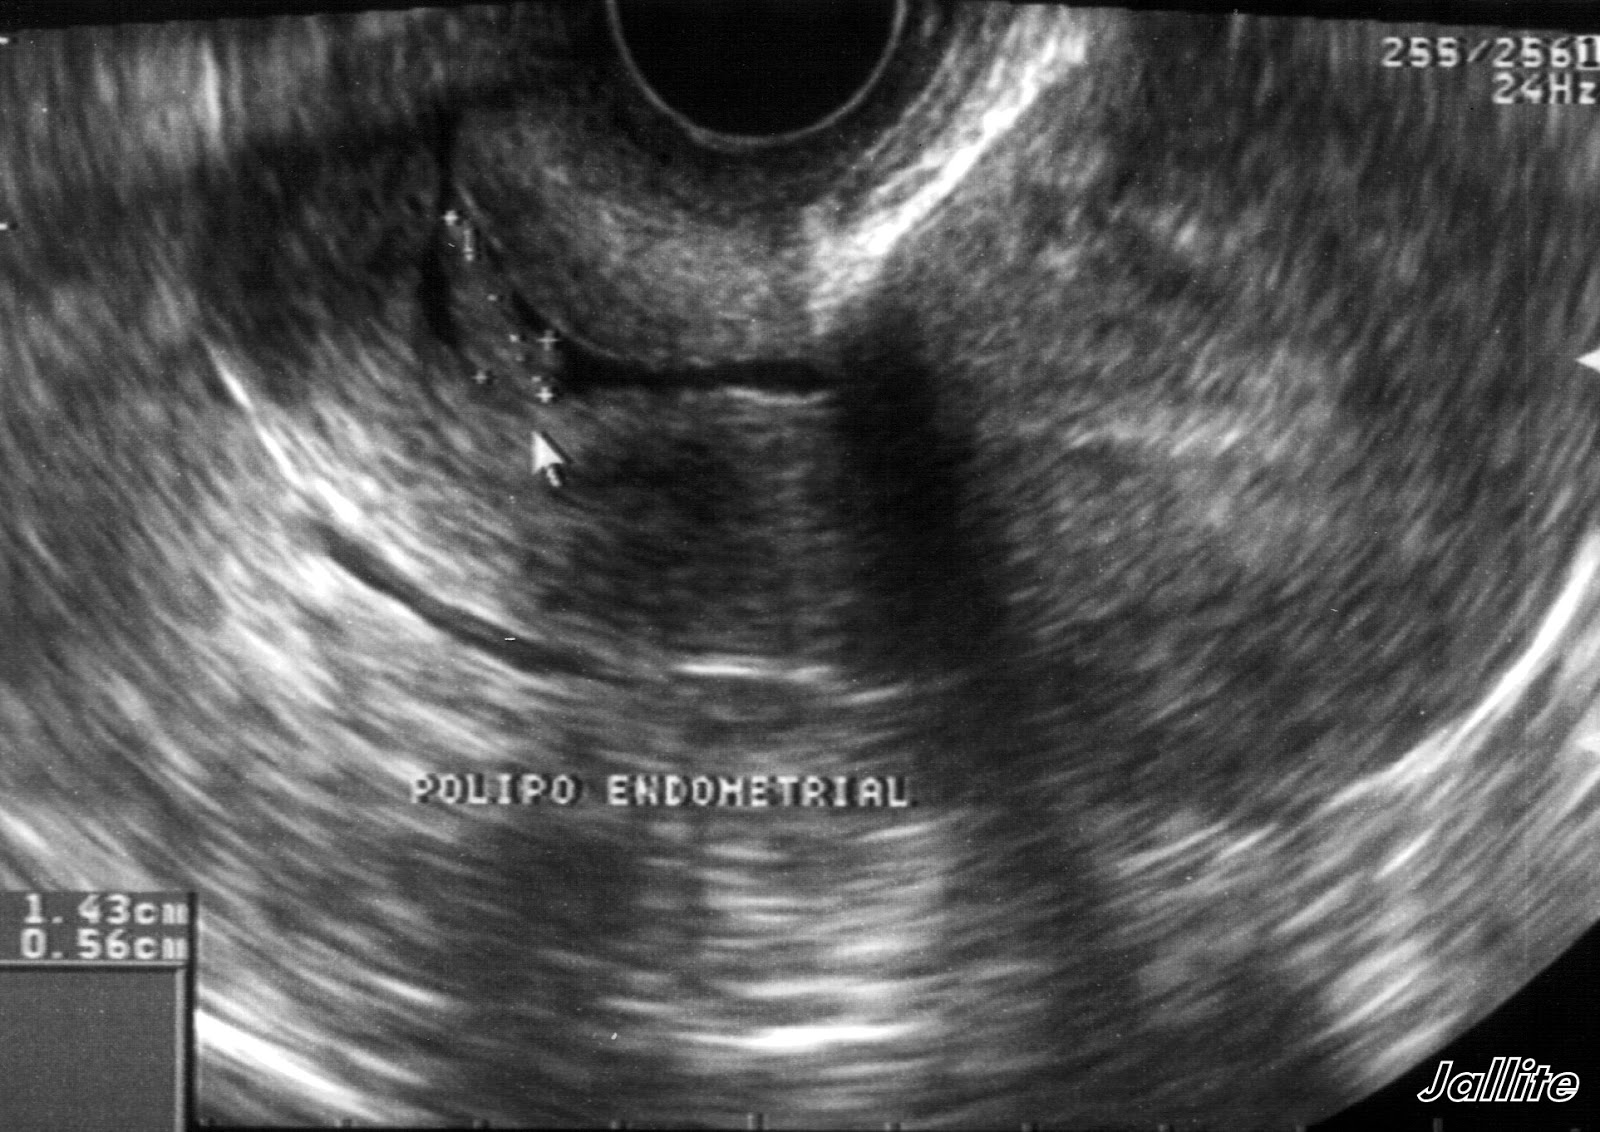

O Que Significa Pólipo Endocervical? Quando falamos em "pólipo endocervical", estamos nos referindo a esses crescimentos específicos que ocorrem no colo do útero. Geralmente, eles são benignos, mas, em alguns casos, podem se tornar malignos, o que é motivo de preocupação. Vamos discutir mais sobre esse aspecto posteriormente neste.. Há dois tipos deles: pólipo endometrial e pólipo endocervical. Neste artigo iremos explicar quais são suas características e a diferença entre eles. Os pólipos endometriais são, como o próprio nome sugere, as lesões que desenvolvem-se no endométrio e, portanto, localizam-se na cavidade uterina. Eles são constituídos a partir do.

O pólipo endometrial se caracteriza como uma saliência sólida localizada no endométrio (tecido que reveste o interior do útero), causada pelo crescimento anormal de células. O seu tamanho varia de 5 mm a 3 cm, podendo ser único ou múltiplo. Esse tipo de tumor benigno é mais comum na menopausa.. Se você recebeu recentemente um diagnóstico de pólipo no útero, fique tranquila. Na grande maioria das vezes, eles são alterações benignas com pequeno potencial de malignização. Pólipos uterinos são projeções da camada mais interna do útero, acima de sua superfície, sendo formados pelos mesmos tipos de célula, porém com um crescimento exagerado.